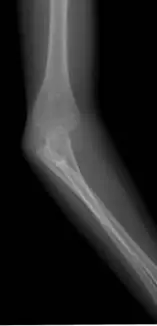

本題提供兩張前臂/肘關節 X 光影像(前後位及側位):

圖二(側位 lateral view):從側面觀察前臂近端,可見橈骨與尺骨的正常解剖關係消失,兩骨在近端呈現骨性連結,無法各自獨立運動,橈骨頭形態異常。

這兩張影像與先天橈尺骨黏合的典型 X 光表現相符:近端橈尺骨骨性融合,橈骨頭形態改變(可伴隨橈骨頭後脫臼),前臂固定於旋前(pronation)位置。